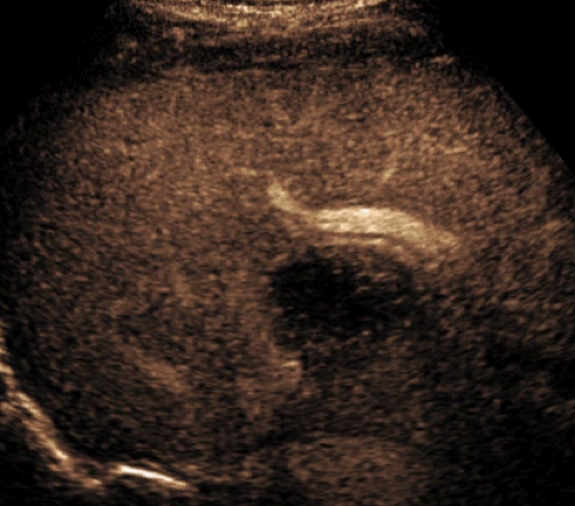

Using Siemens Healthineers ultrasound equipment, these bubbles can be imaged in two distinct contrast-based imaging modes: contrast pulse sequencing and contrast harmonic imaging.

According to Brian, “CPS has a three-pulse sequence that allows us to get deeper into the body. You can see the bubbles a little quicker and they look bigger than they would in the alternate mode. It’s going to provide a better penetration of the ultrasound, making it ideal for most scans involving adults.”

“CHI gives us a higher resolution image for evaluating smaller lesions or lesions with smaller vessels,” said Brian.

Once the procedure is in progress, the contrast goes through three distinct perfusion phases that last up to six minutes. These include the arterial, portal and late phases.

During this phase, the contrast enters the arteries of the liver to begin the imaging. Being a dynamic modality, a sonographer can capture this early flow consistently.

“The arterial phase is important for a lesion such as a focal nodular hyperplasia,” said Brian. “You'll see a central feeder artery and the vessels that branch off of it, like spokes off of a wheel.”

Missing this early phase, which can be common with other modalities, is not a concern when using contrast-enhanced ultrasound.

Once the arterial phase is complete, the ultrasound professional can begin to visualize the contrast flowing through the portal system and filling the liver.

“It is important to see both the arterial and portal phases to be able to accurately diagnose a lesion. Again, being a dynamic modality, you can visualize the flow of contrast in each separate phase without worrying about missing anything,” said Brian.

During the final phase, the liver takes in as much contrast as possible until it reaches equilibrium and starts to wash out.

“Different lesions show different filling patterns, with some lesions, such as large hemangiomas, for example, taking a long amount of time to completely fill with contrast.”

Each of these phases is very important for accurate diagnosis. Throughout the procedure, you can monitor the contrast to determine where the bubbles travel, how fast the lesion fills, how quickly it washes out, etc., all in a real-time manner. That makes this type of imaging incredibly versatile.